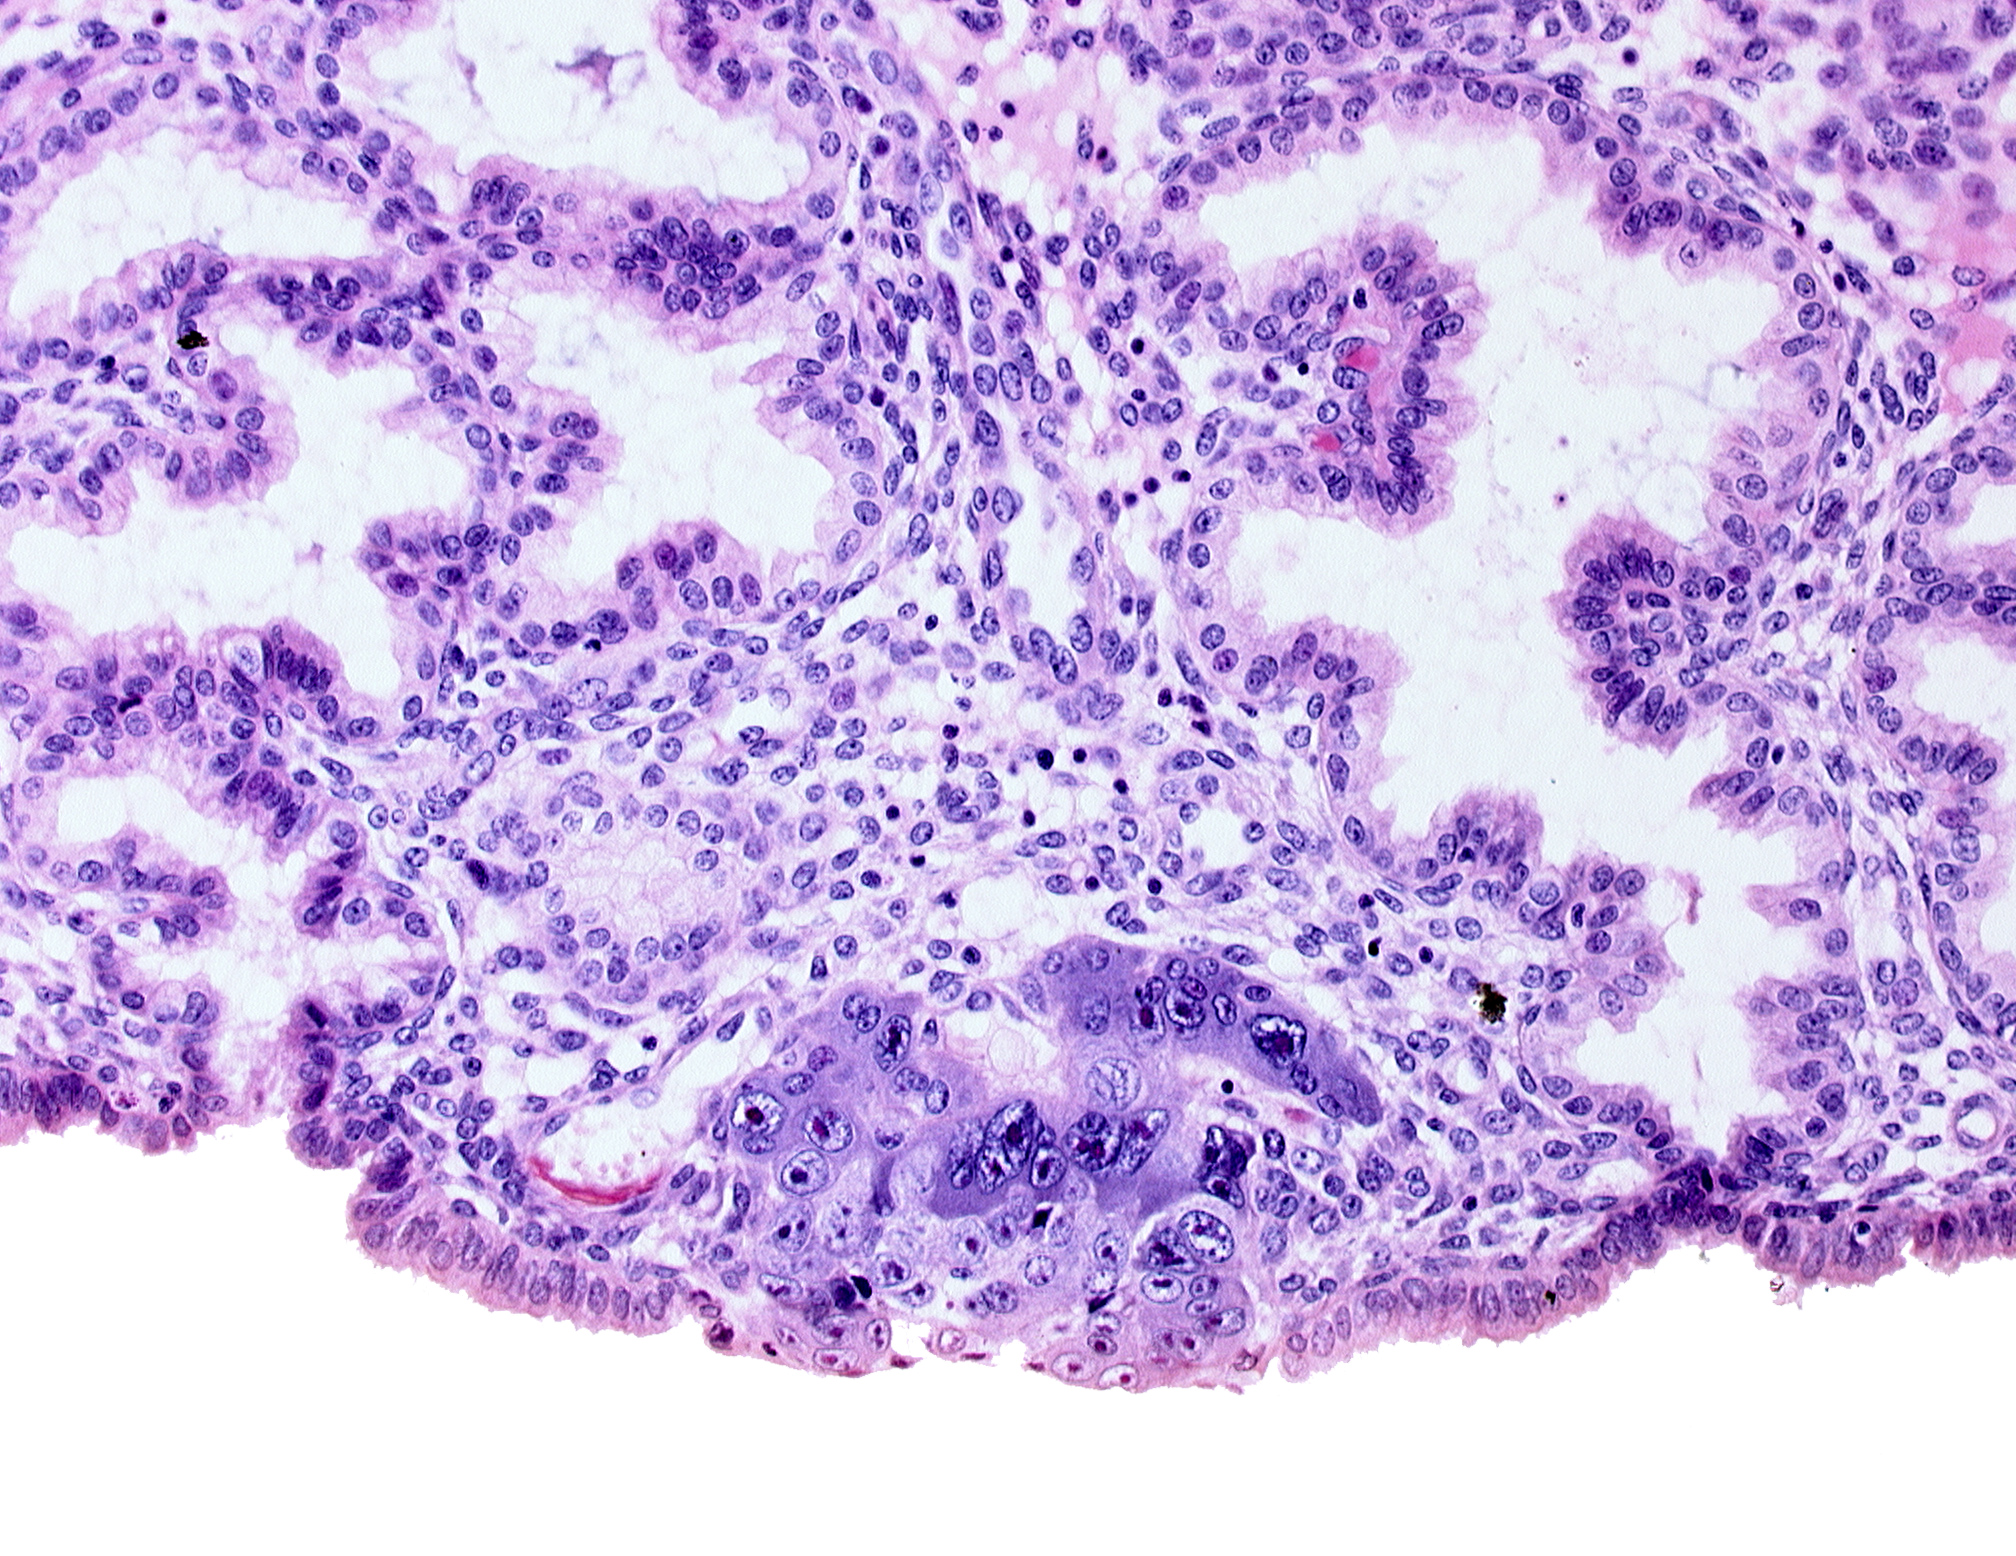

Carnegie Embryo #8155 | Location: 04-01-09

Keywords: blastocystic cavity (blastocoele), endometrial epithelium, endometrial sinusoid, membranous trophoblast at abembryonic pole, syncytiotrophoblastic mass, uterine cavity

Source: The Virtual Human Embryo.